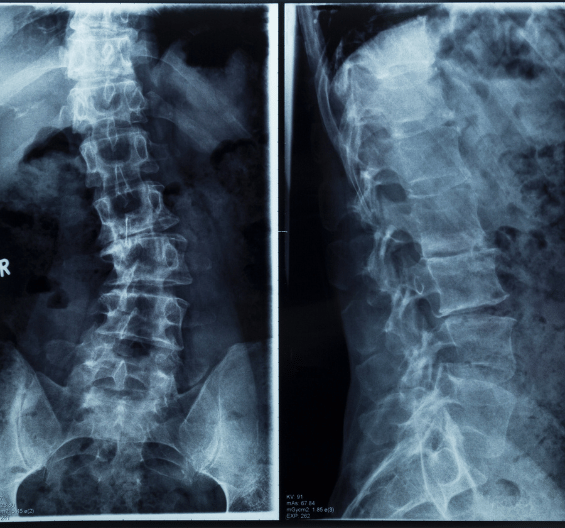

Momentum Spine uses smartphone video technology to create a precise 3D model of the spine — providing a safe and easy alternative to frequent X-rays for children with scoliosis.

Eliminates harmful radiation exposure by replacing repeated X-rays with advanced 3D imaging technology.